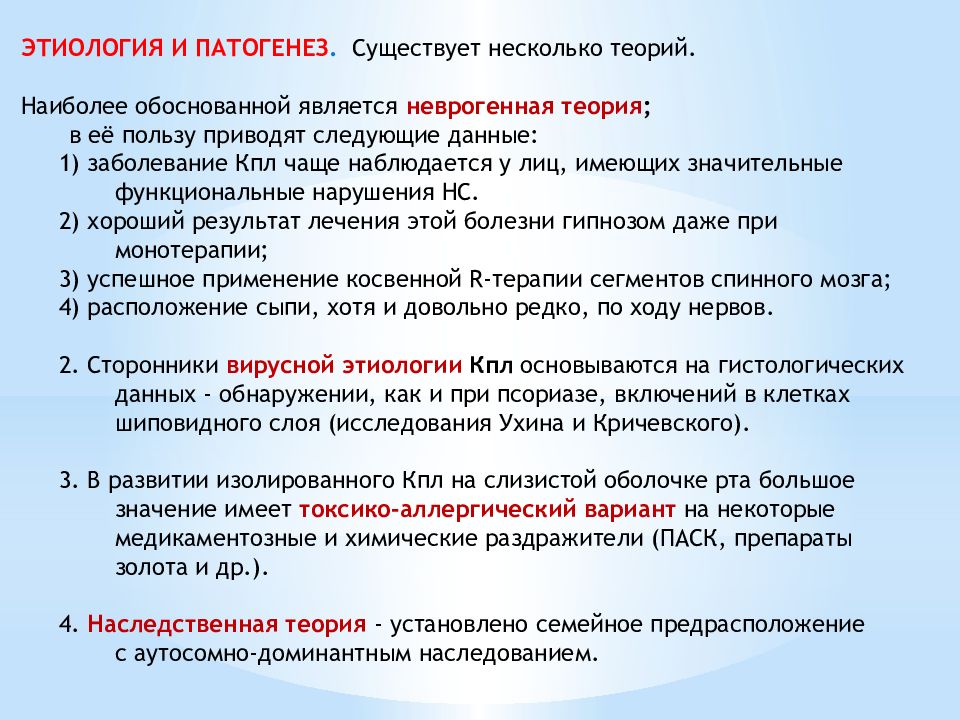

Фото Красного Плоского

Фото Красного Плоского 103 фото